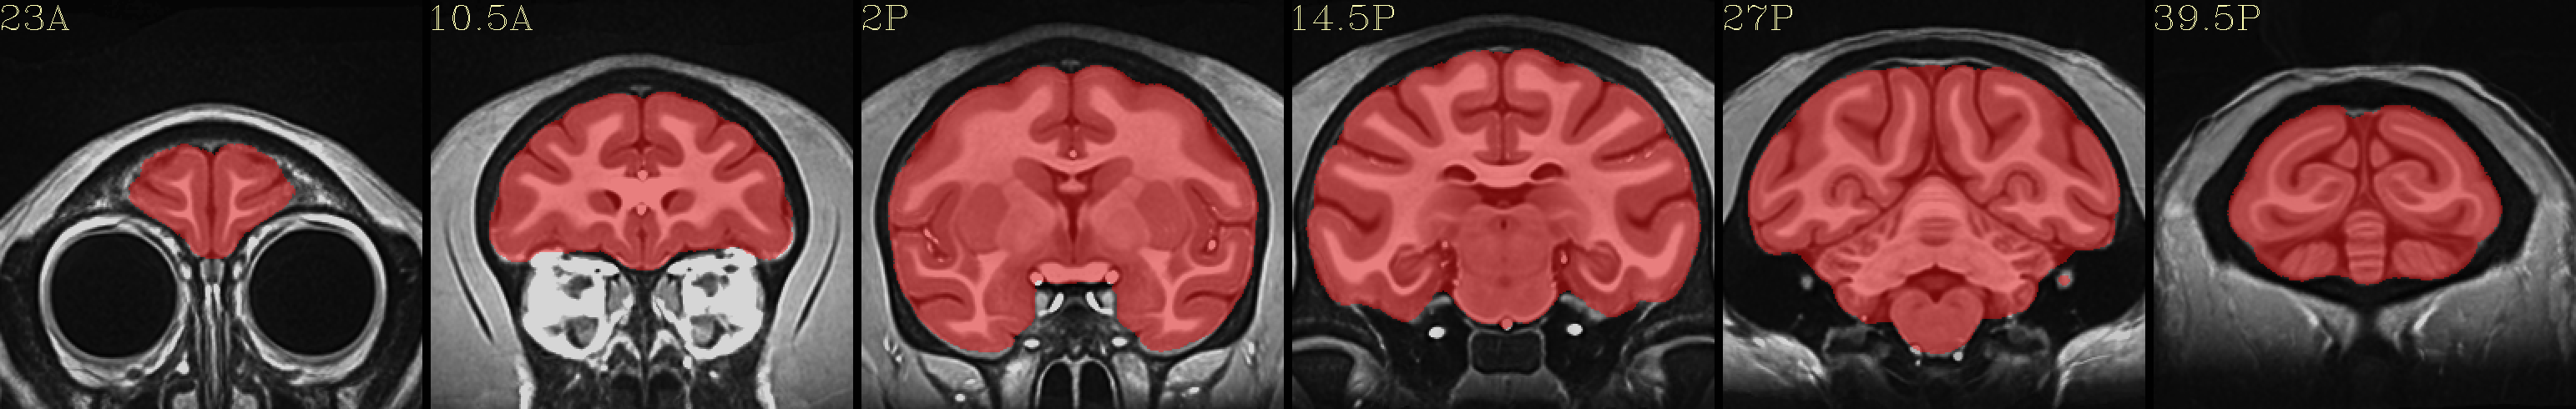

Example images¶

Full NMT with brainmask |

|---|

|

Skull-stripped NMT with 4-tissue segmentation |

Skull-stripped NMT with D99 atlas |

The script used to make these images with ``@chauffeur_afni`` is

here: do_view_nmt_v1.3.tcsh